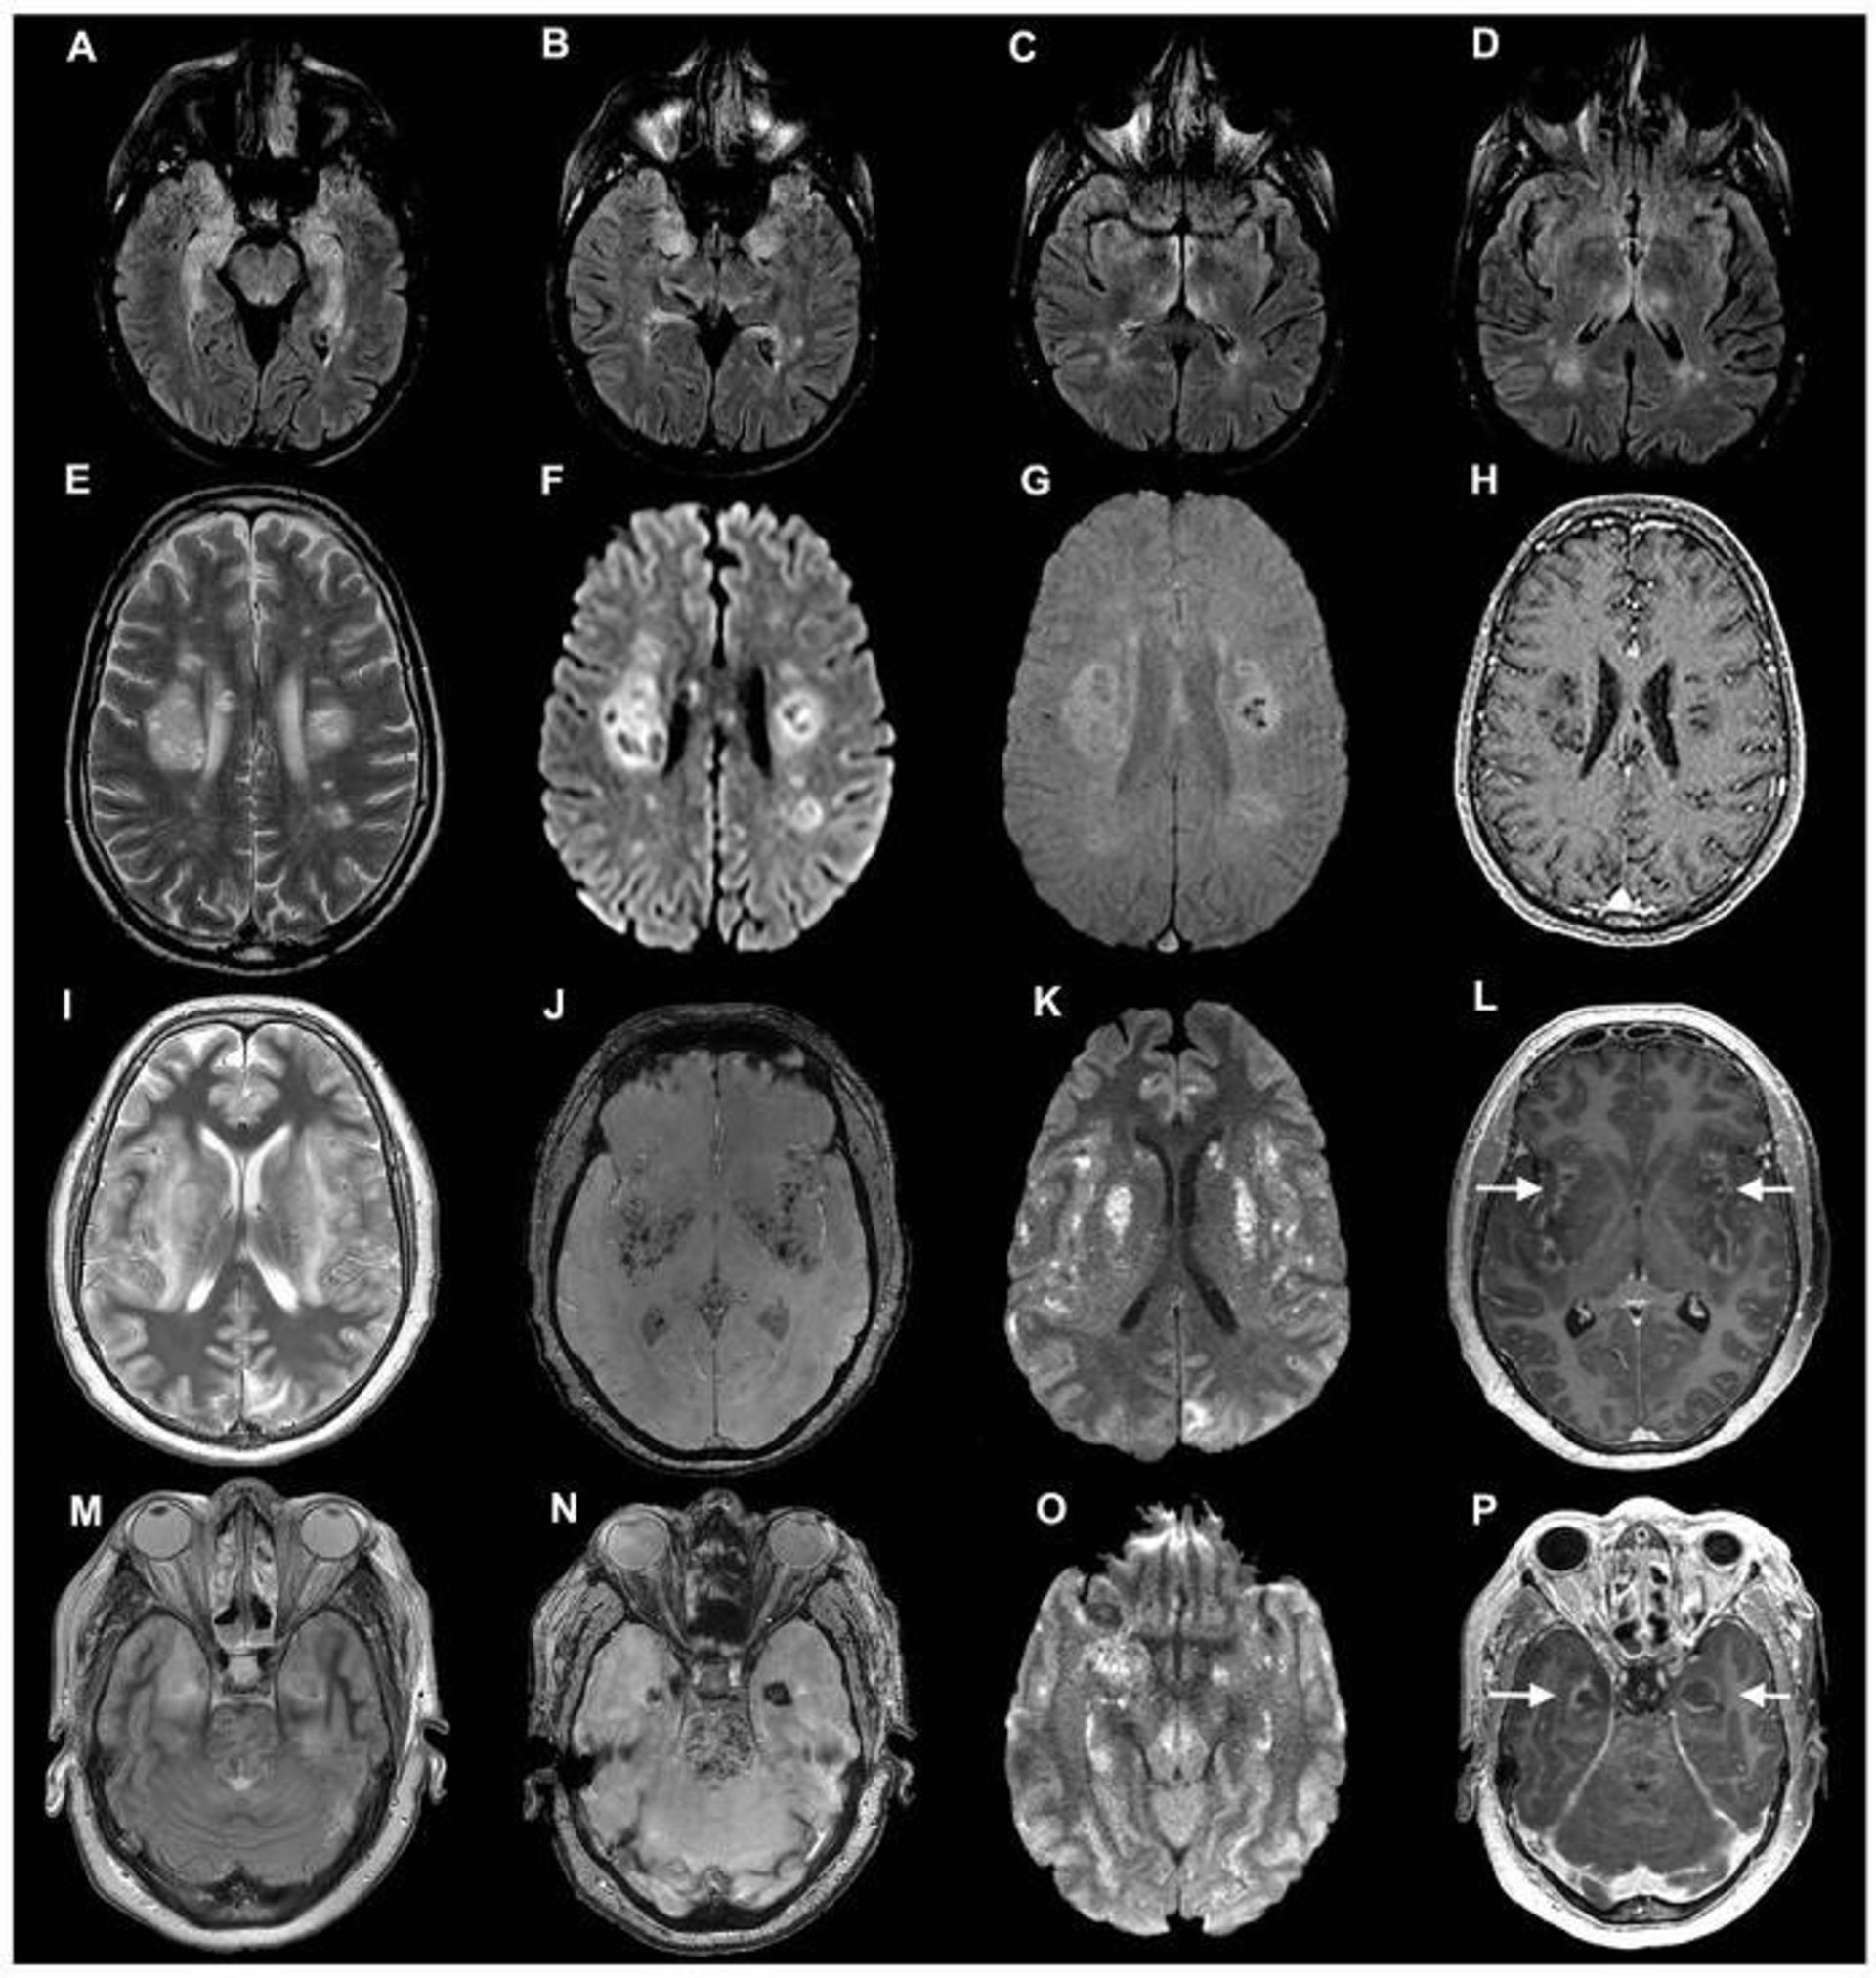

اسکن مغز بیماران کووید ۱۹

اسکن‌های مغز بیماران مبتلا به کووید ۱۹ از مطالعه‌ای که در ماه جولای منتشر شد. دانشمندان متوجه شدند برخی از بیماران دچار عوارض عصبی جدی نظیر آسیب عصبی می‌شوند